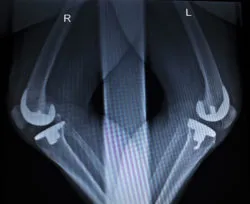

Two X-rays show knees with implants.A knee replacement patient says the bone cement used in some knee implant procedures is defective. She says the cement failed and caused loosening of the implanted device.

Plaintiff Osa G. filed this DePuy lawsuit over problems with a knee implant. The lawsuit was filed against DePuy Orthopedics due to alleged injuries sustained by the plaintiff after receiving a device adhered with the DePuy SmartSet HV bone cement knee implant. Loosening of the device can cause pain, total device failure, and the need for revision surgery.